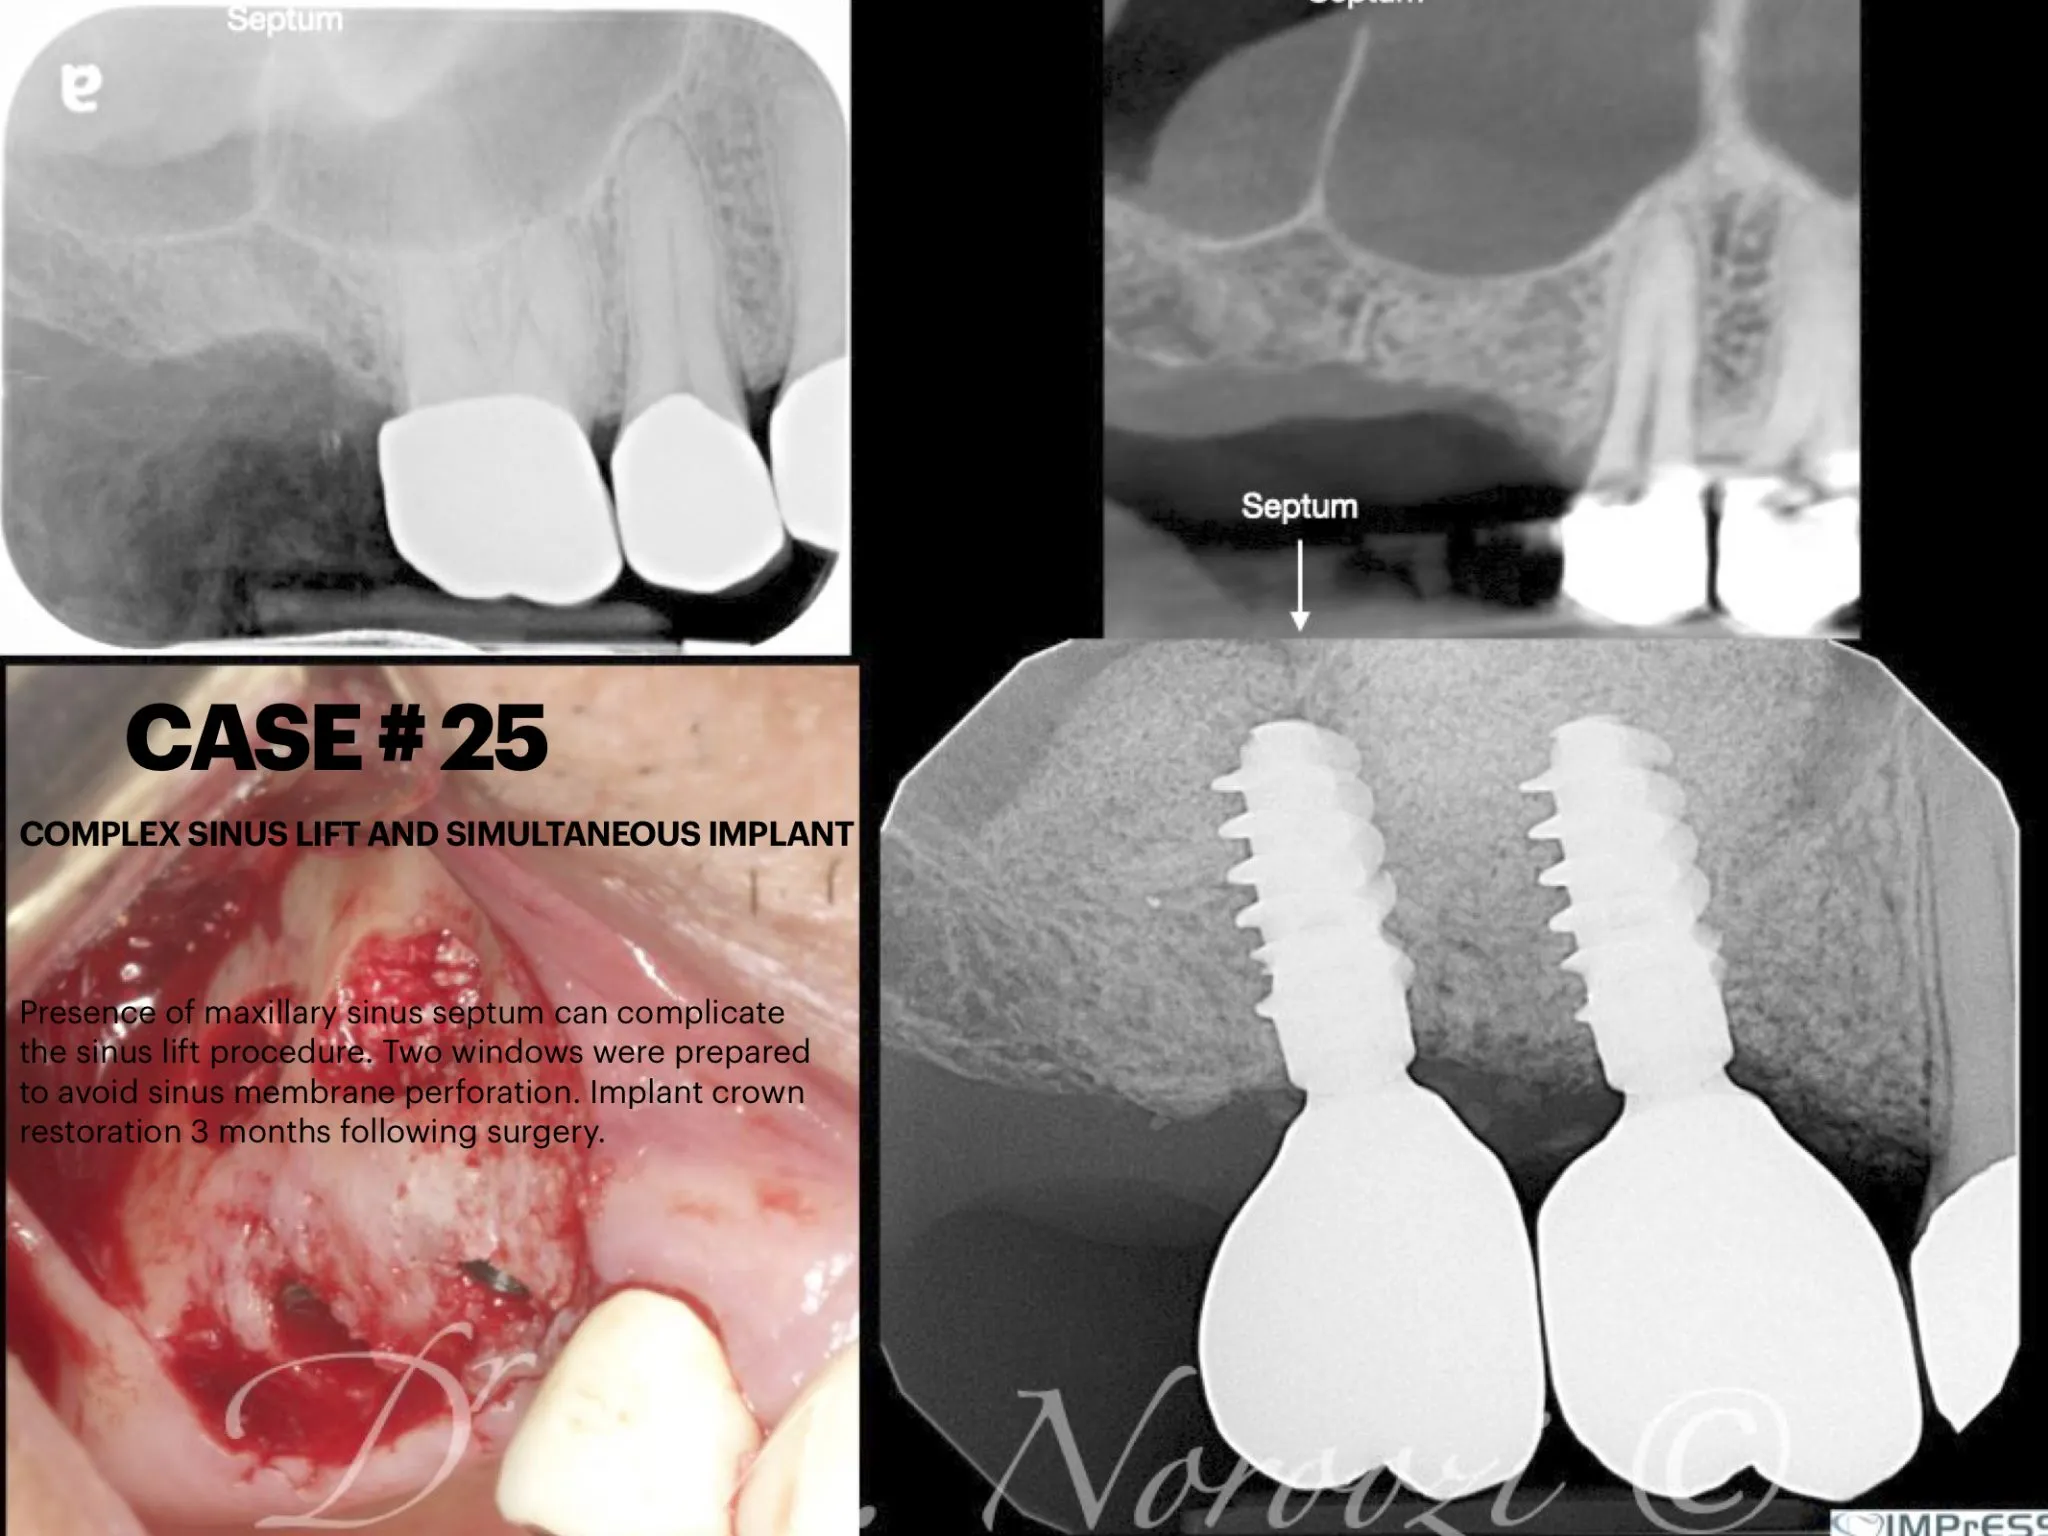

Before & Afters of Dental Implant Patients

Complete Dental Implant Cases Gallery

Surgical advances with SAME-DAY IMPLANTS in Vancouver BC

Using the most recent advances in dental implant technology, Dr. Noroozi is able to place single stage implants. These implants do not require a second procedure to uncover them but may require a minimum of six weeks of healing time before artificial teeth are placed. There are even situations where the implant can be placed at the same time as the tooth extraction and the artificial tooth can be inserted immediately following the implant placement – further minimizing your number of surgical procedures.

General Disclaimer: The results in the photographs are examples only and do not imply any certainty of the result of a procedure, and all outcomes are subject to the circumstances of the individual patient.